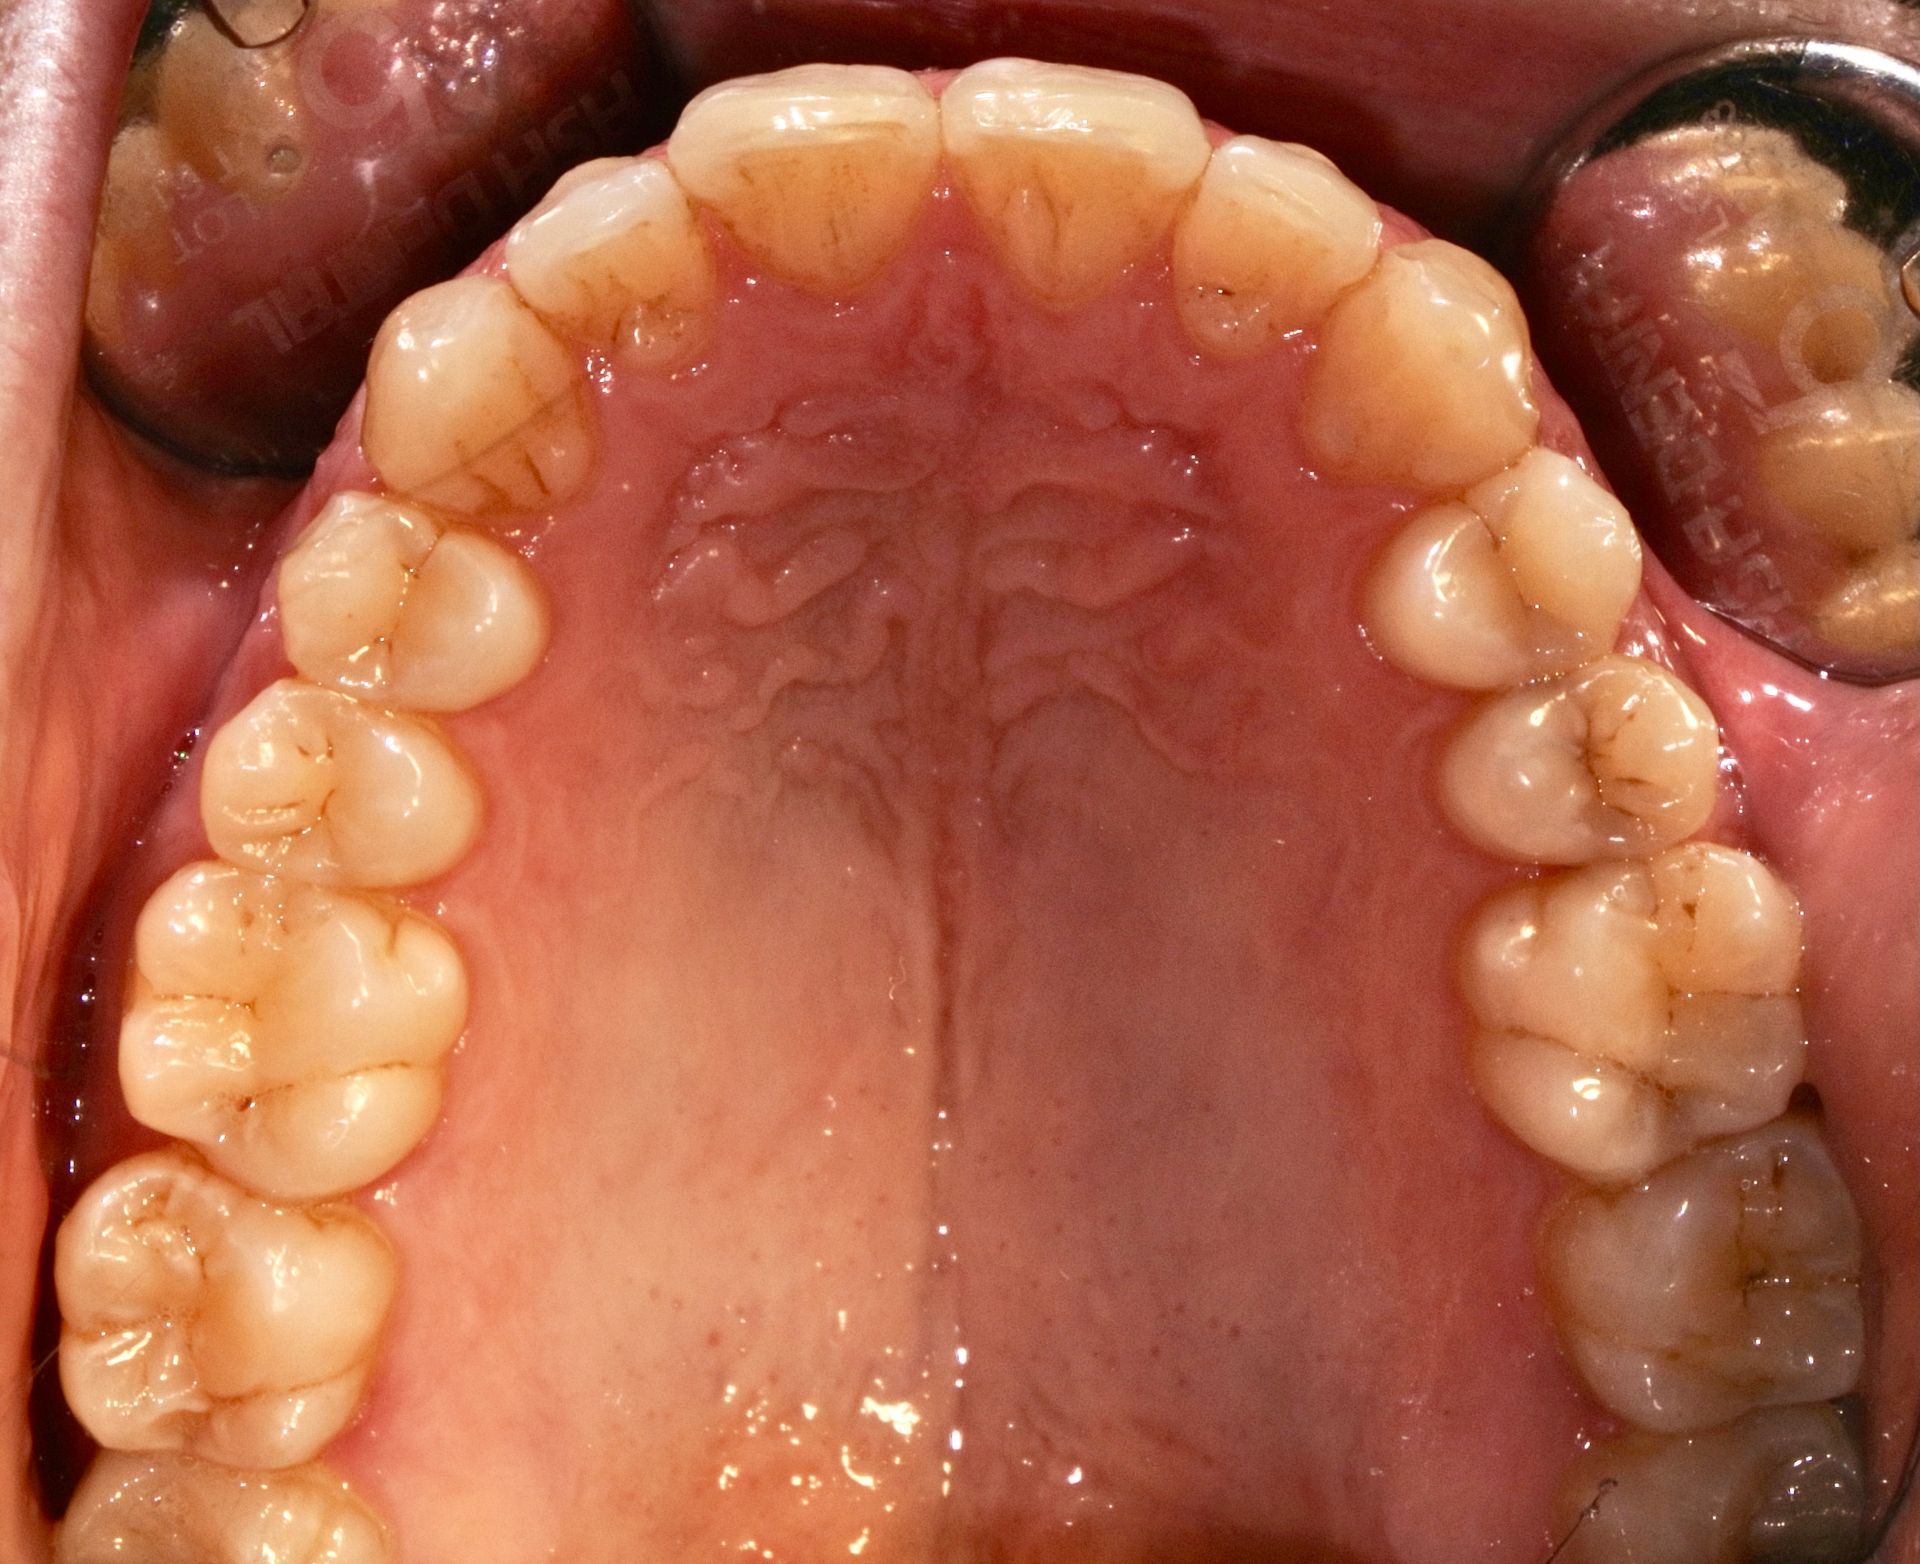

INVISALIGN è un sistema di mascherine trasparenti (aligner) studiato per permettere una elevata predicibilità dei movimenti dentali e della durata del trattamento.

Si tratta di una soluzione invisibile ed efficace per l'allineamento graduale dei denti.